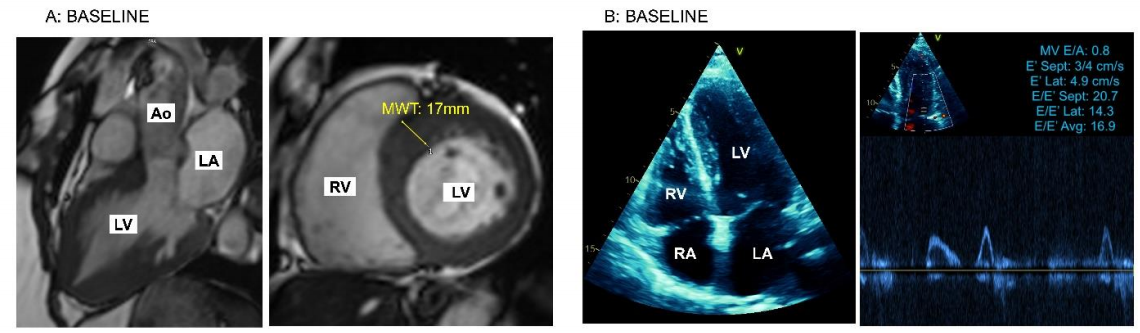

心脏磁共振:确诊HCM,LVEF 60%,无晚期钆增强,提示无显著心肌纤维化(图1A);

运动负荷超声:明确排除左心室流出道梗阻(图1B);

舒张功能:E/A比0.8,E/E'平均值高达16.9(提示明显舒张功能障碍);

图1.基线心脏磁共振和超声